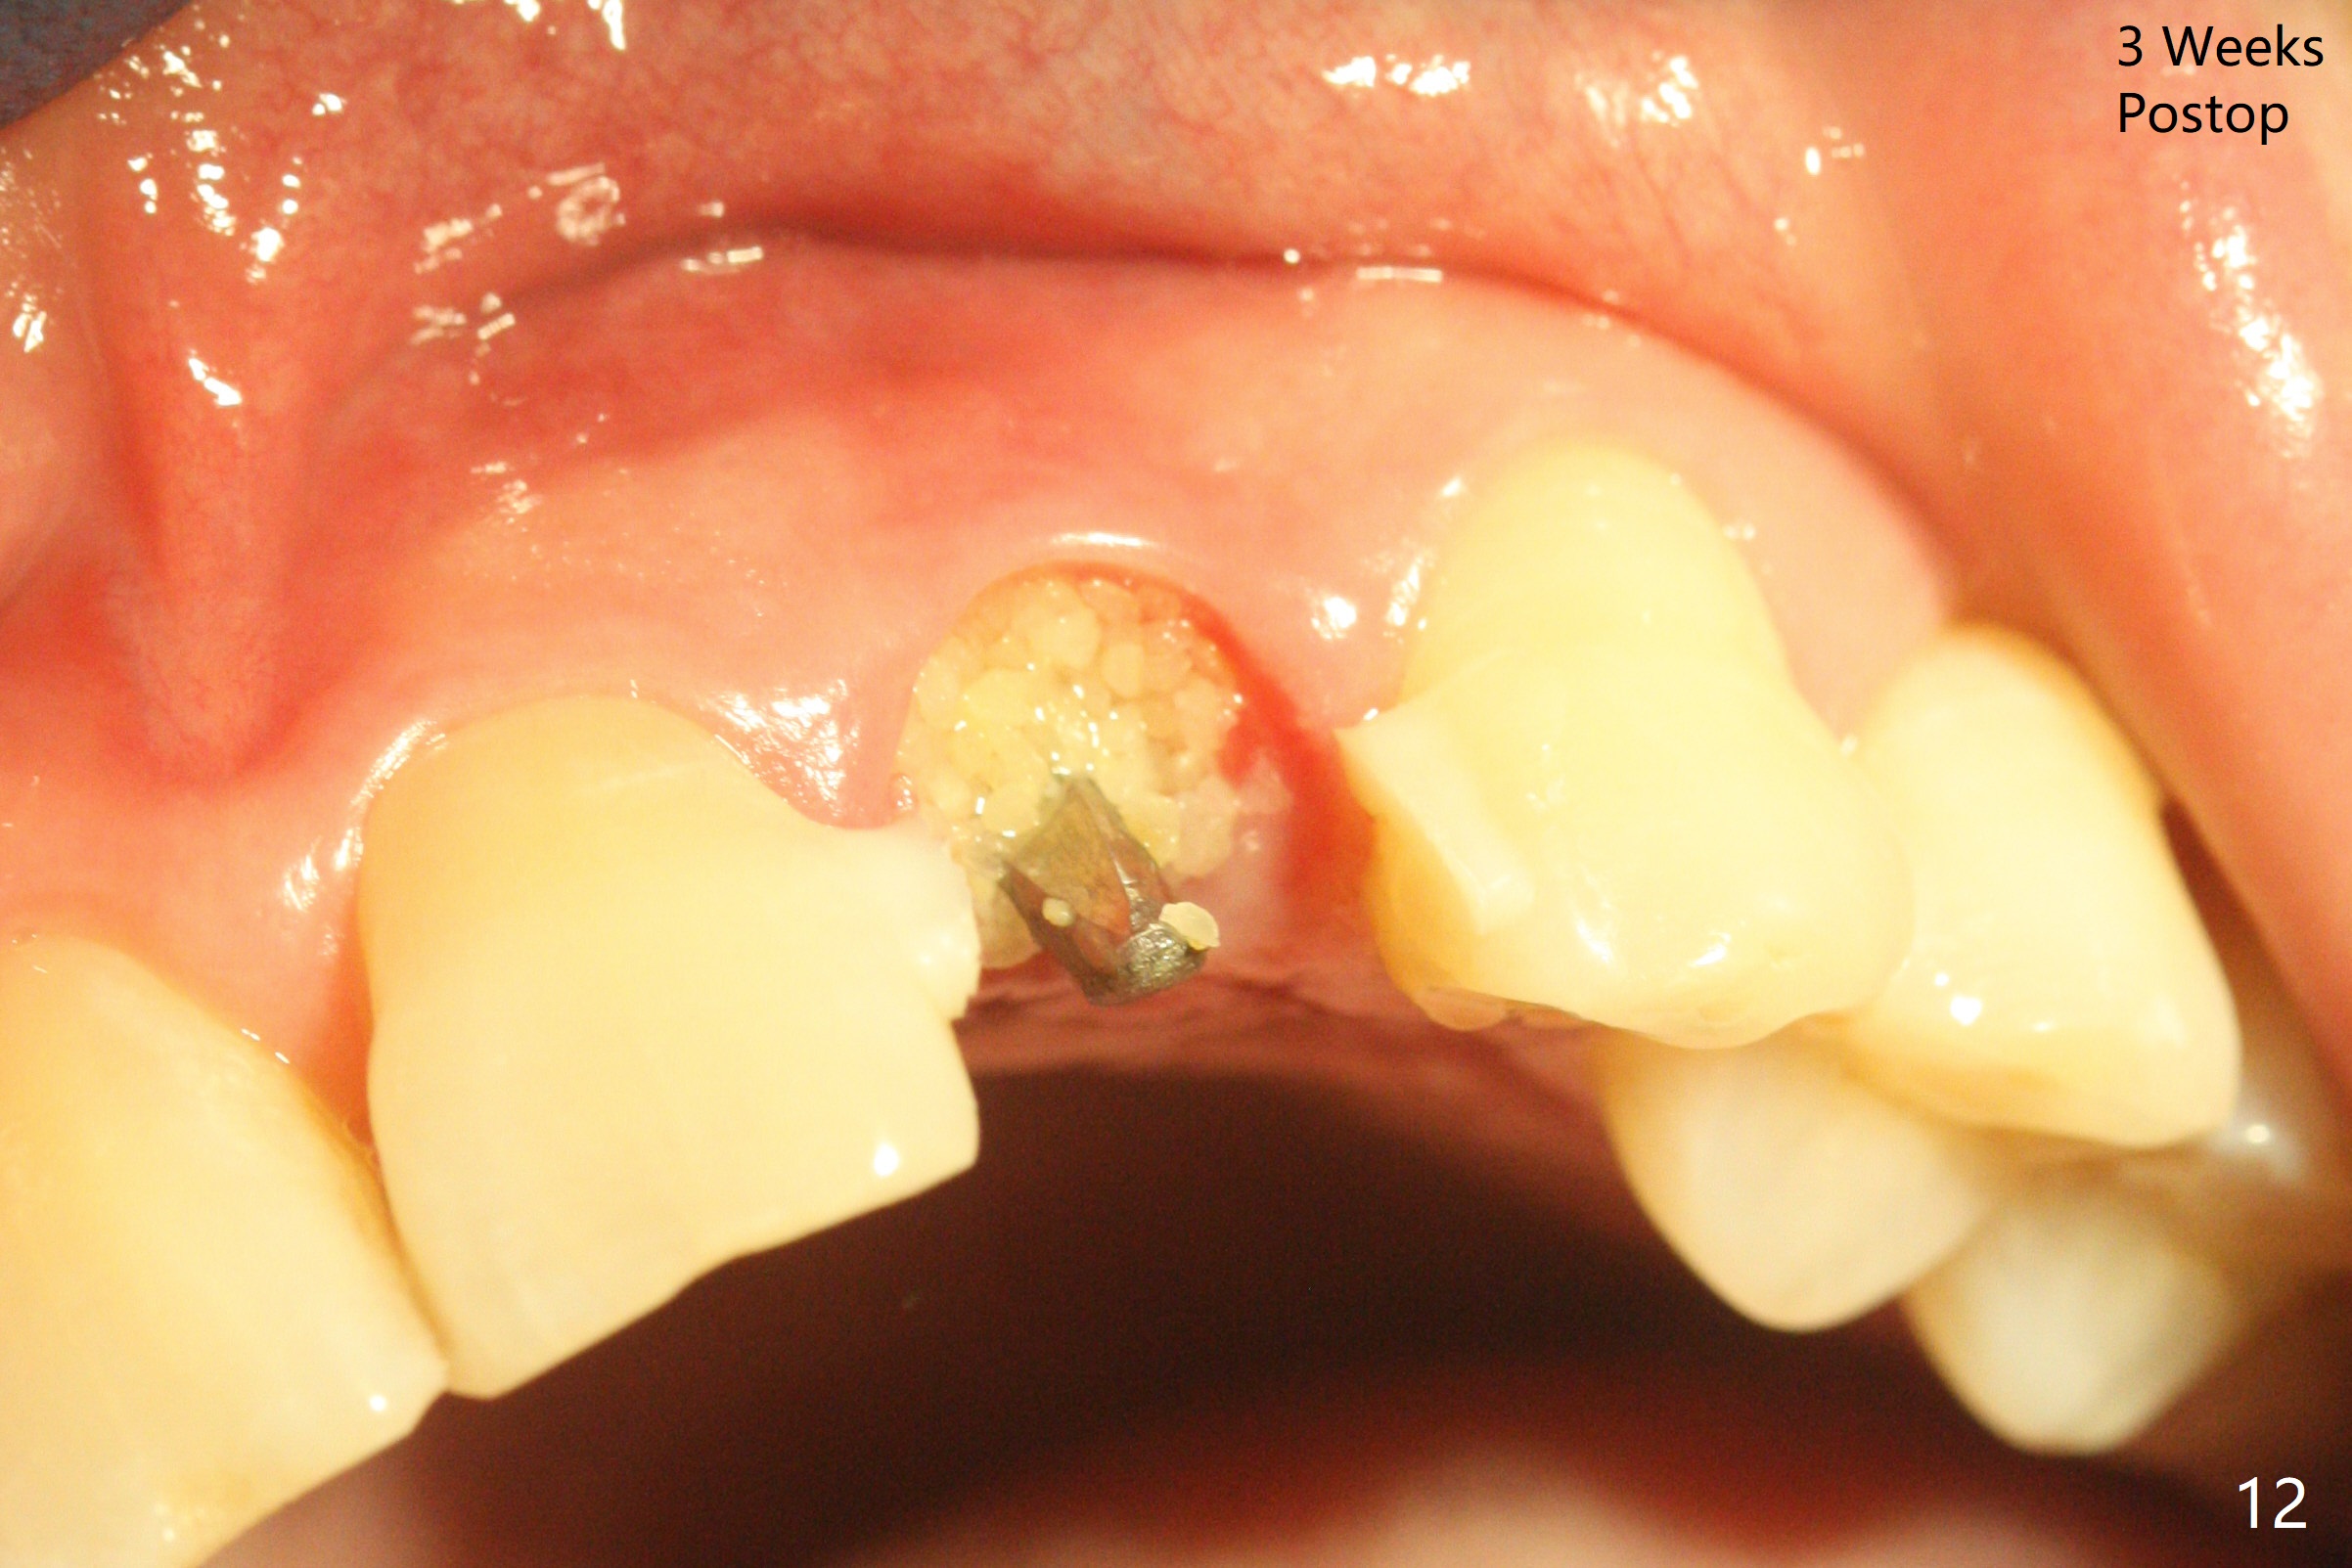

病人回来带来瘘道(图一),不过不会增加难度,病牙去除,它便自动消失。尽管颊侧骨壁完全失去,颊侧牙龈仍丰满(图二),为什么呢?第一,因为粗大牙根存在,第二两旁牙齿,牙槽骨撑着帐篷(侧切牙颊侧牙龈),第三,牙冠。为了防止术后牙龈塌陷,尽量不切开,即刻放置植体(牙根);由于前牙缘故,这次植体不能很大,所以植骨必须过度(over grafting),最后即刻制作临时牙冠,撑住牙龈。这就是所谓每个人进入角色。这个牙根有一种先天性畸形:dens in dent (图三(腭侧观):箭头)。尽管腭侧牙根畸形,腭侧骨壁吸收临床上并不严重,所以钻洞仍偏腭侧。当预定最后钻头还在钻洞时,填入大量粘性骨块(图四:*),细长植体还没有完全卡入鼻底(图五),最后好像可以(图六,七)。植体,骨粉入位(图八),最后临时牙冠出场(图九)。尽管植体小,术后一周临时牙冠仍然可以维持牙龈原有形状(emergency profile,图十:箭头(*:树脂强化牙冠固定))。图十一以不同角度显示瘘道缩小。术后三周取出有些松动的临时牙冠,骨粉虽然还没有被肉芽组织整合,但是显得正常,周围牙龈健康(图十二)。术后4个月牙龈形态正常(图十三),没有触痛;颊侧骨板轻度凹陷(图十四);骨粉仍在原位(图十五)。术后7个月骨粉仍在原位(图十五,十六,但是冠部密度减低(可能骨粉流失,需要牙周或者树脂敷料保护)),没有螺纹暴露。但是牙冠边缘暴露,说明牙龈收缩(图十七,与图十三对比),颊侧骨板仍塌陷(图十八)。插入龈线取得多个目的:修整基台边缘,取模,颊侧牙龈推向颊侧,有利于即将衬里牙冠龈缘进入龈下(图十九)。取模后牙冠边缘(图二十:<)衬里,然后修整,变窄,以便插入龈下,促进颊侧牙龈下降(图二十一,二十二)。术后8个月牙冠粘固前牙龈健康(图二十七,八),牙冠(图二十九)固位后,病人满意(图三十),咬合调整(图三十一),注意腭侧粘固粉流出通道(<)。